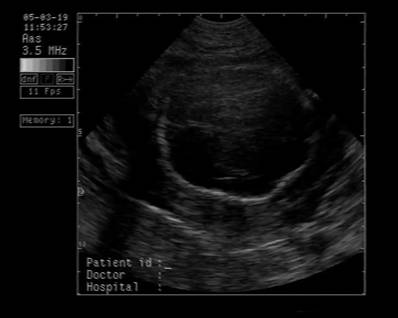

Fig. nr.250. Ciclopie diagnosticata la 17 sapt.

Fig. nr.251 Ciclopia din imaginea precedenta ,cu defect de inchidere pe linia mediana a fetei